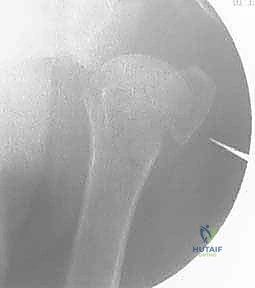

- الأشعة السينية (X-rays): يتم أخذ صور من زوايا متعددة (أمامية خلفية، جانبية، وإبطية) لتحديد نوع الكسر وموقعه.

- التصوير المقطعي المحوسب (CT Scan): في الكسور المعقدة (ثلاثية أو رباعية الأجزاء)، يُعد التصوير المقطعي ثلاثي الأبعاد ضرورياً جداً. فهو يمنح الجراح خريطة دقيقة لحجم الشظايا العظمية ومواقعها، مما يساعد في التخطيط الجراحي الدقيق قبل دخول غرفة العمليات.

4. إدخال الأسلاك المعدنية (K-wires)

بمجرد أن يصبح الكسر في الوضع المثالي، يتم إدخال أسلاك كيرشنر (Kirschner wires) الدقيقة عبر الجلد مباشرة إلى العظم. يتم توجيه هذه الأسلاك بزوايا هندسية مدروسة لضمان أقصى درجات الثبات. عادة ما يتم استخدام 2 إلى 4 أسلاك.